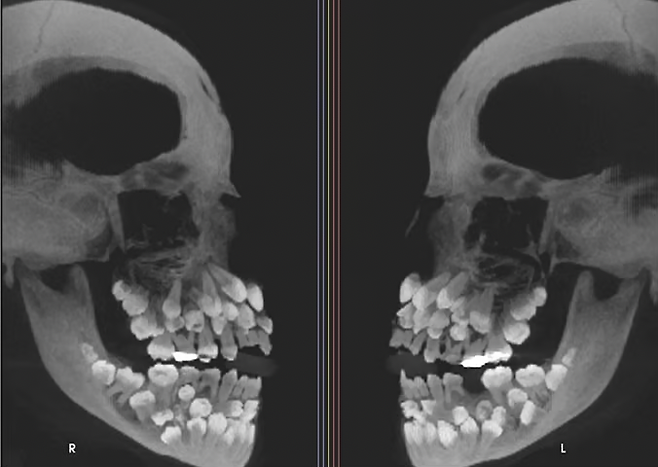

지난 15일 VN익스프레스 등 외신은 브라질에 사는 11세 소녀가 위쪽 유치 1개를 뽑기 위해 병원을 찾았는데 엑스레이 촬영 결과 소녀의 입안에서 유치 18개와 영구치 32개, 과잉치 31개 등 총 81개 치아가 발견됐다고 보도했다.

11세 소녀 입 안에서 치아가 무려 81개나 발견돼 학계에 충격을 주고 있다. 지난 15일 VN익스프레스 등 외신은 브라질에 사는 11세 소녀가 위쪽 유치 1개를 뽑기 위해 병원을 찾았는데 엑스레이 촬영 결과 소녀의 입안에서 유치 18개와 영구치 32개, 과잉치 31개 등 총 81개 치아가 발견됐다고 보도했다.

일반적으로 성인 기준 32개인 정상 치아 수를 넘는 추가 치아가 발견되는 것을 '다발성 과잉치증(multiple hyperdontia)'으로 부른다. 이 질환은 잇몸 속에 치아가 매복돼 있어 정상 치아의 맹출(잇몸 위로 나는 과정)을 방해하거나 치아 배열이 어긋나는 등의 문제를 일으킬 수 있다. 또한 매복된 과잉치 주변에 물혹이 생기는 등 다양한 문제가 유발될 수 있다. 다발성 과잉치증은 선천적인 것으로 대개 1~2개의 과잉치만 발견되는 경우는 종종 있다. 일반적으로 합병증을 유발할 가능성이 있는 과잉치는 발치를 권장하며, 특히 어린아이의 경우 영구치 맹출에 방해가 되지 않도록 조기에 발치하는 것이 좋다. 발치 후에는 치아 배열을 위해 교정 치료가 필요할 수 있다. 다만 이번 사례처럼 30개가 넘는 과잉치가 확인된 사례는 전 세계적으로도 매우 드물다. 해당 사례는 브라질 미나스제라이스주 주이스지포라 연방대학교 치과병원 연구팀이 진료 중 확인한 것으로 미국 치과교정·악안면외과학회지에 보고됐다.